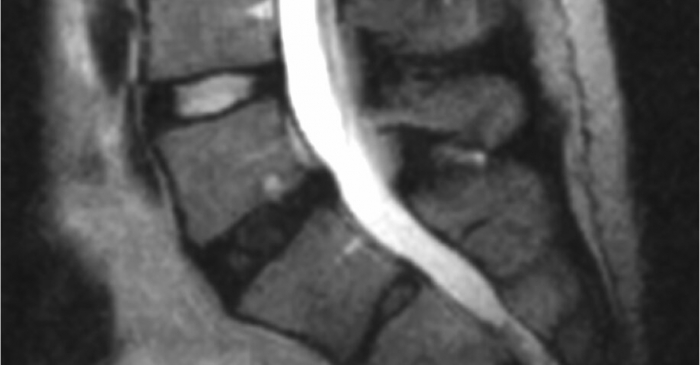

Degenerative disc disease (DDD)

Degenerative disc disease, frequently referred to as DDD, is a term that describes changes in the spinal disc occurring with age. Let us look at those changes, whether they may be the source of pain, and what treatments are available.